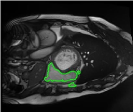

4.3 Comparison with cardic MR images for right ventricle segmentation

Cardiac MRI images often suffer from intensity inhomogeneity due to the varying magnetic susceptibility of cardiac tissues. This can lead to ambiguous boundaries, making it hard for models to consistently identify the left ventricle. Moreover, the heart is composed of several complex anatomical structures, including chambers, valves, and surrounding tissues. Accurately delineating the borders between these various components can be difficult, especially when they are closely positioned or exhibit similar intensity characteristics. In this section, we demonstrate the effectiveness of the RefLSM in segmenting cardiac MR images. The cardiac MR images are standardized to a size of . To enhance the credibility of the proposed model, we segmented 5 cardiac MR images compared the results with 6 other models, including the ALF [MA2019201], LoGRSF [DING2017224], ABC [WENG2021115633], RESLS[8765635], ICTM [WANG2022108794] and FeaACM [XUE2024110673] models. Fig. 5 displays the partial results from all the segmentation models. It is clear that the segmentation results from the RefLSM closely align with the ground truth of the left ventricle segmentation. However, the ALF model demonstrates relatively poor ability to capture the overall structure of the left ventricle; it exhibits limitations with precise boundary detection, particularly in areas of intensity inhomogeneity. Consequently, the evolution curve of the ALF fits into an unstable wave-like result. Suffering from intensity inhomogeneity and surrounding anatomical structures, the LoGRSF model, ABC model and RESLS model all represent over-segmentation and under-segmentation to some extent. Additionally, the results in the 6th column of Fig. 5 show multiple instances where where the ICTM model inaccurately identifies adjacent myocardial tissues as part of the left ventricle due to their similar intensity, leading to false positives. While the FeaACM demonstrates some ability to segment the left ventricle, it is not robust and fails to segment the 5th row of Fig. 5. The 2nd and 3rd rows also include small adjacent excessive regions. In contrast, our proposed model demonstrates marked improvements in accurately capturing the left ventricle’s boundaries. It effectively addresses challenges associated with severe intensity inhomogeneity and noise, resulting in better segmentations. The proposed method appear to maintain better structural integrity in the segmented images, closely aligning with the ground truth.

To quantitatively measure the segmentation results of each model, we compute the Dice and Precision values for left ventricle segmentation. Moreover, we opted for a voilin plot to effectively compare the RefLSM with six other models, as shown in Fig. 7. The results clearly demonstrate that the RefLSM yields superior Dice and Precision values than the other representative models, indicating its closer alignment with the ground truth and highest segmentation accuracy.